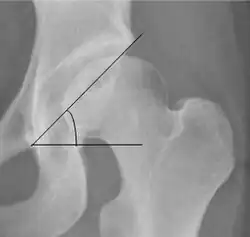

Tönnis angle | ![]() |

Slope of the sourcil (the sclerotic weight-bearing portion of the acetabulum) | 0 to 10°

|